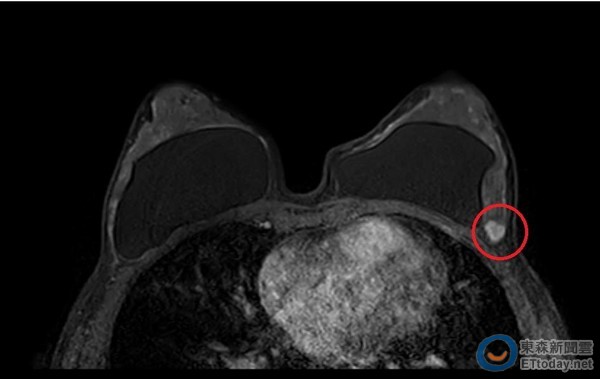

▲乳癌常見死角-乳房腋尾位置圖。(圖/澄清醫院提供,以下皆同。)

此病患在觸摸到不明腫塊後,立刻預約乳房磁振造影(MRI)及高解析度超音波檢查,透過影像看到0.9cm的腫瘤,經超音波導引切片和病理檢驗確診為一期乳癌,由於該受檢者的腫瘤位置為乳腺末端的乳房腋尾,若不是發現得早,是很容易被忽略的死角。

▲病患磁振造影像。